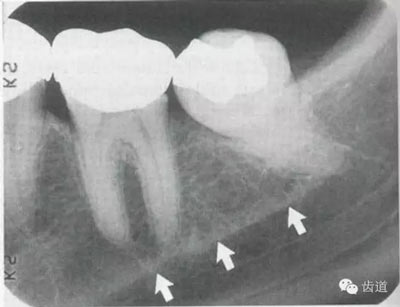

位于前磨牙根尖區(qū)域,為一大致圓形密度低的影像。頦孔位置變異大,多位于第二前磨牙根尖稍下,注意與根尖周病變區(qū)別,其要點(diǎn)是牙周膜及其骨硬板是否連續(xù)不斷。

位于磨牙牙根尖下方,呈寬約為0.4cm凹面向下邊緣整齊的帶狀密度低的影像,其兩側(cè)有密度高的線條狀影像,為下頜管骨密質(zhì)